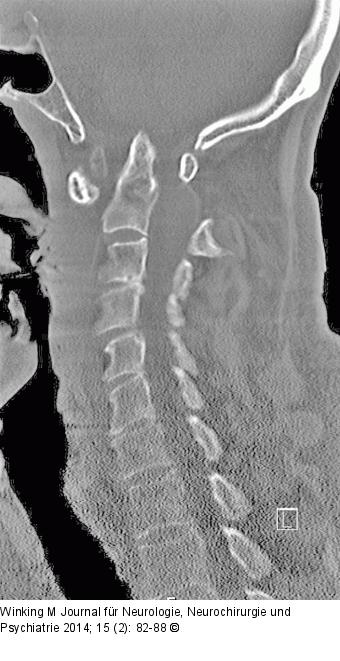

Abbildung 1: Rheumatische Wirbelsäule Sagittales Computertomogramm mit Darstellung einer atlanto-axialen Instabilität und signifikanter Einengung des Zervikalkanals in Höhe von HWK 1/2. |

Sagittales Computertomogramm mit Darstellung einer atlanto-axialen Instabilität und signifikanter Einengung des Zervikalkanals in Höhe von HWK 1/2. |